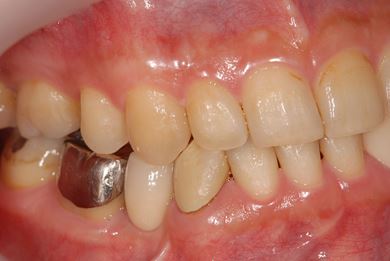

骨再生インプラント治療

| 性別/年齢 | 男性 / 34歳 | ||||||||||||||||||||||||||||||||

| 治療方針 | ソケットリフトにて上顎洞を拳上し、インプラント治療を可能にする。 | ||||||||||||||||||||||||||||||||

| 治療内容 | インプラント1本(ソケットリフト)、メタルボンドセラミッククラウン1本 | ||||||||||||||||||||||||||||||||

| 総治療費 | 547,838円 | ||||||||||||||||||||||||||||||||

| 治療期間 | 4ヶ月 |